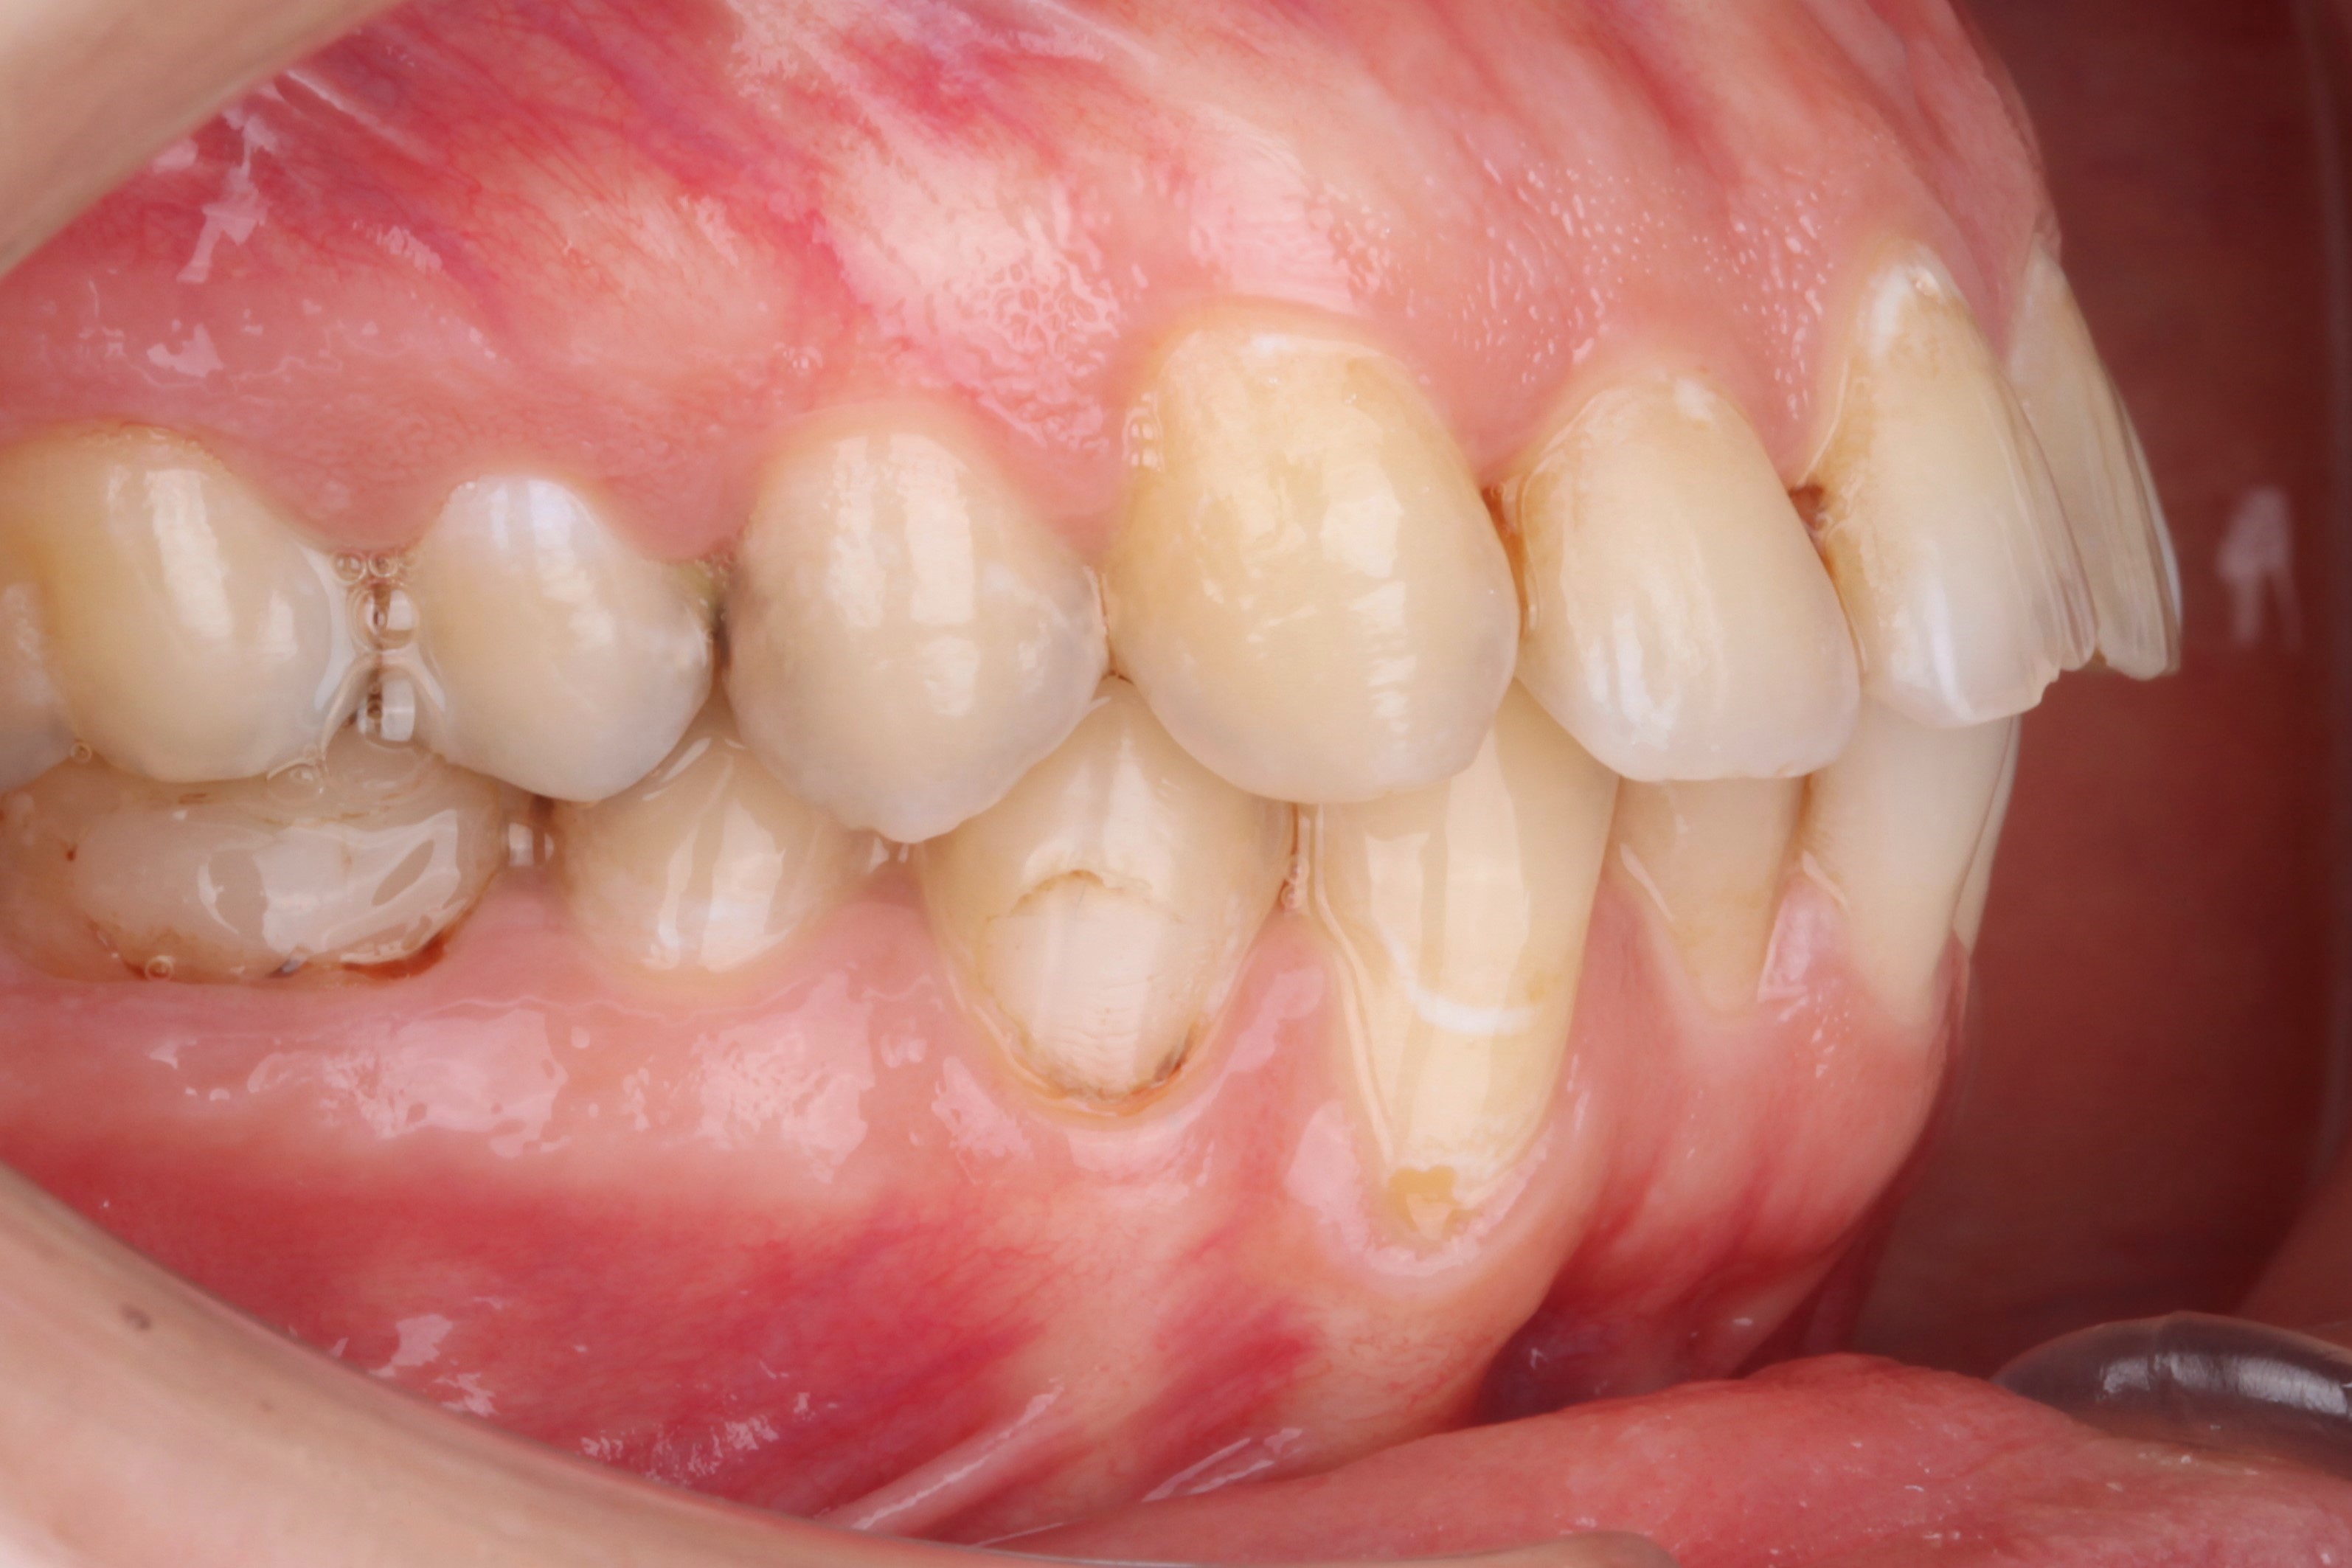

К нам обратилась пациентка 27 лет с желанием сделать красивую улыбку с ровными и красивыми зубами. На фотографии мы видим выраженные рецессии десны на нижних клыках, несостоятельные пломбы, скученность и стираемость.

В данной клинической ситуации было принято решение провести санацию полости рта, затем закрыть рецессии в области нижних клыков и только потом приступить к ортодонтии.

Спустя месяц пациентка с уже санированной полостью рта была направлена на закрытие рецессий. Терапевт произвёл закрытие рецессий десны композитным материалом. Также было запланировано пришлифовывание материала в полости рта и закрытие небольшой рецессии на зубе 4.4.